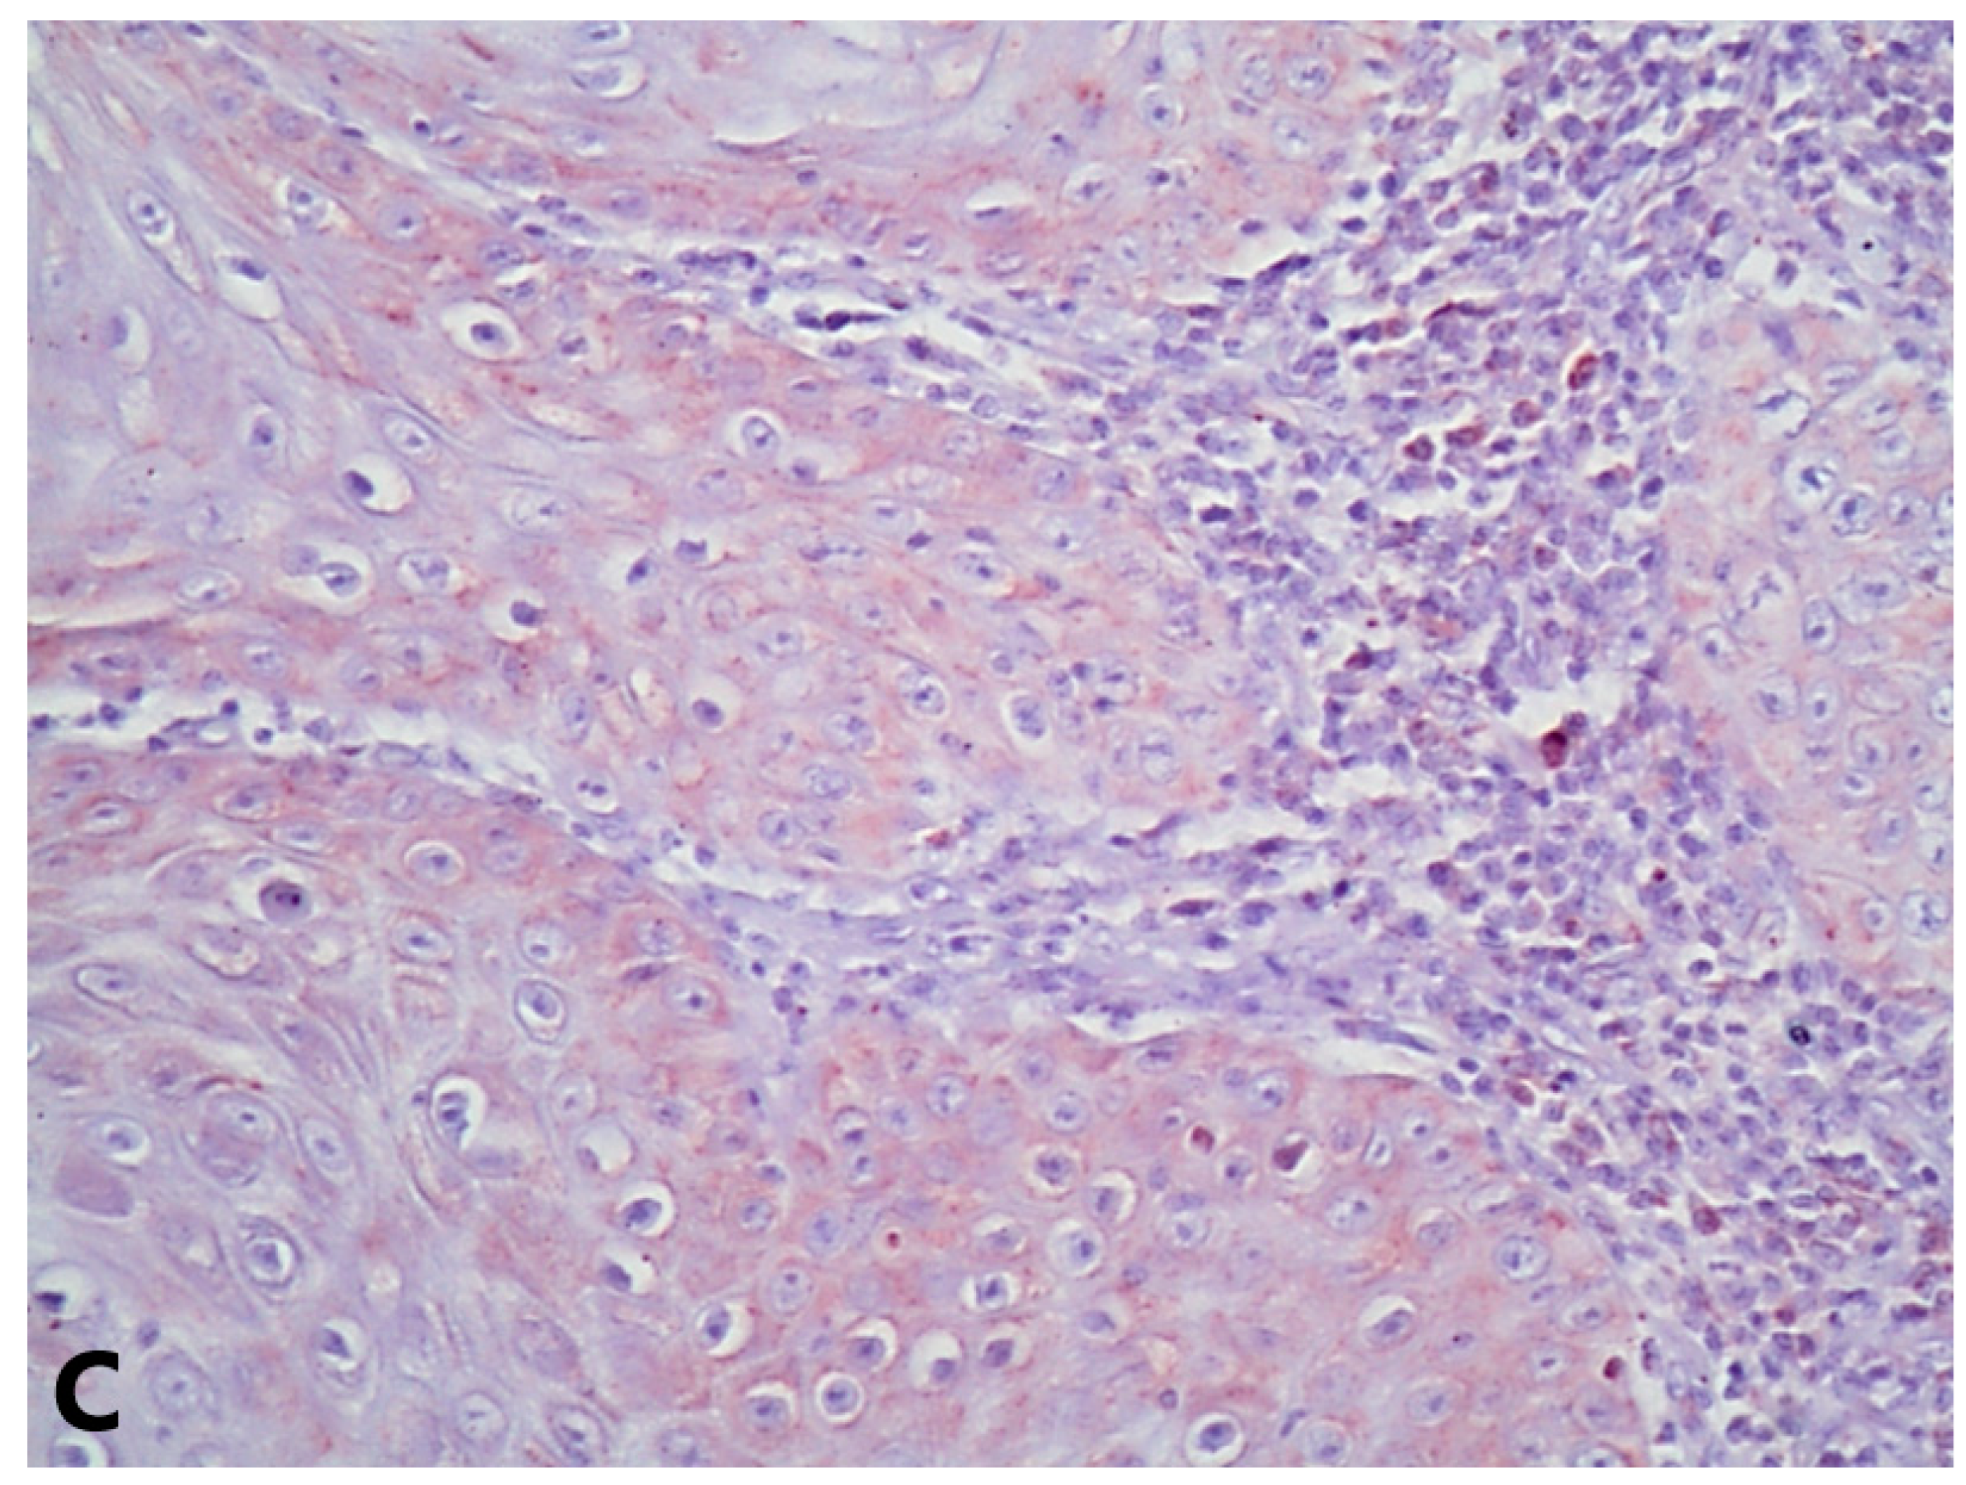

3. Results

3.3. VDAC1 Expression